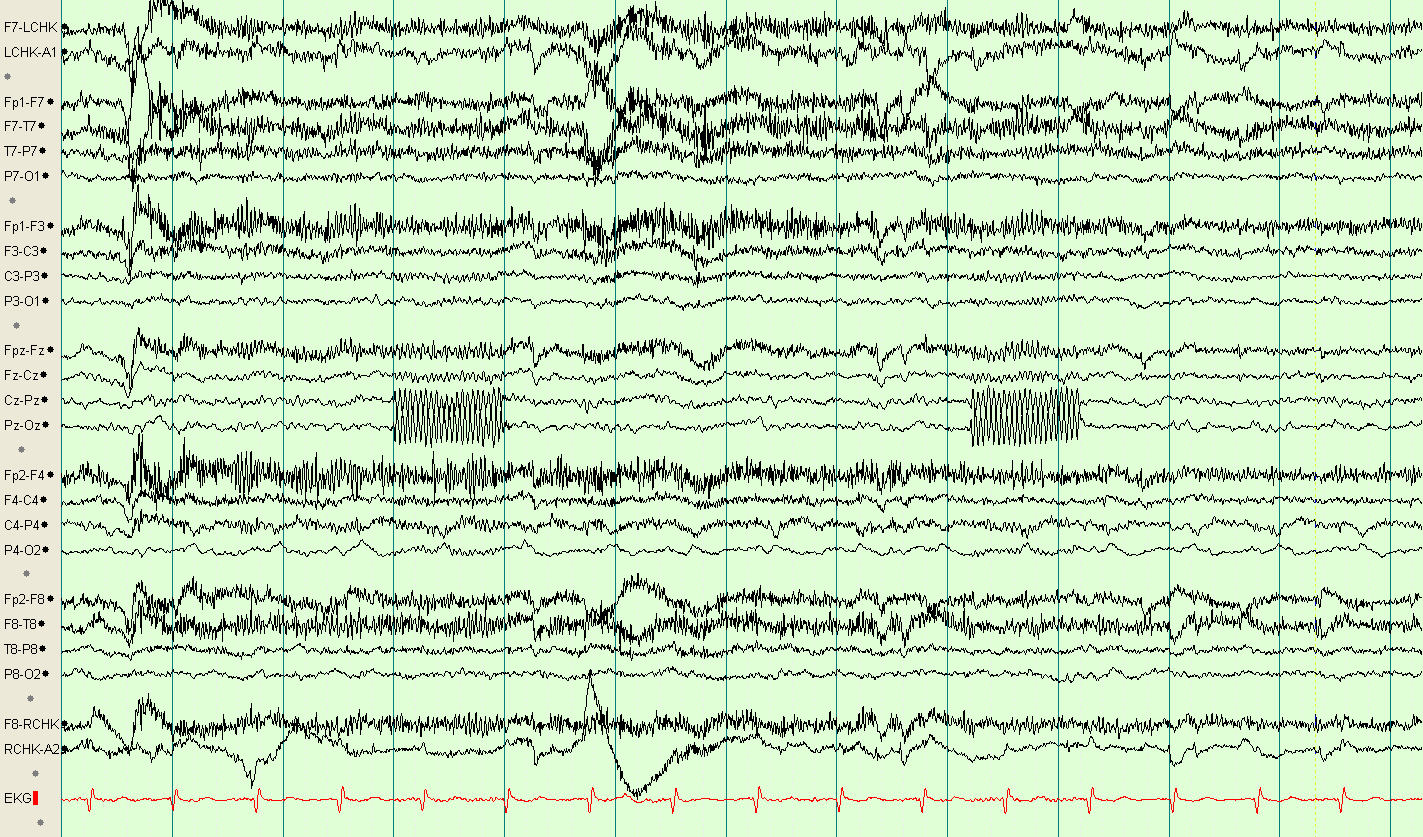

Roving Eye Movements

eegatlas-online.com

eegatlas-online.com

eye roving movements artifacts eegatlas online

Roving Eye Movements

eegatlas-online.com

eegatlas-online.com

artifacts eye roving movements eegatlas online

Lateral Eye Movement

eegatlas-online.com

eegatlas-online.com

artifacts eye movement lateral eegatlas online

Lateral Eye Movement

eegatlas-online.com

eegatlas-online.com

eye lateral movement artifacts eegatlas online

Lateral Eye Movement

eegatlas-online.com

eegatlas-online.com

artifacts eye movement lateral eegatlas online

Lateral Eye Movement

eegatlas-online.com

eegatlas-online.com

eye movement lateral artifacts online eegatlas